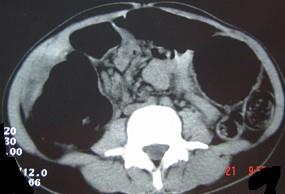

问题 女,30岁,便秘、腹痛腹胀多年,CT检查如图,最可能的诊断是 ( )

选项 A、结肠肠扭转 B、结肠肠栓塞 C、先天性巨结肠 D、结肠肠套叠 E、结肠肠梗阻

答案 C